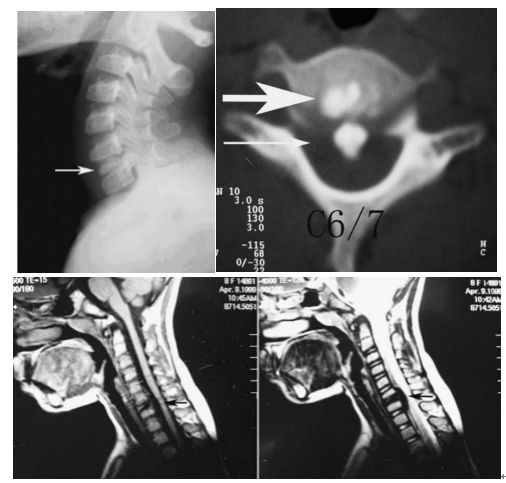

典型病例【病例1】

图:患者8岁,女孩,因严重颈部疼痛、活动受限伴左上肢无力、麻木不适2天就诊。既往有锁骨骨折、额部软组织挫伤病史。查体:颈椎活动受限,左上肢肌力正常,但感觉减退。白细胞、血沉、CRP升高。颈椎侧位片和CT平扫提示C6-7椎间盘钙化(粗箭头)和后纵韧带骨化(细箭头),颈椎MRI提示C6-7水平脊髓明显受压。给予颈椎制动、枕颌带2.5kg颈椎牵引2周。随后,颈托固定1个月。2年后随访复查颈椎CT如下图,同时上述症状完全缓解。

图:2年后复查CT示C6-7钙化的椎间盘和后纵韧带骨化都消失了